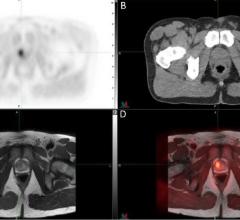

The Netherlands Cancer Institute (NKI) announced it has received funding from the Dutch Cancer Society (KWF Kankerbestrijding) to test whether a novel molecular imaging technology can guide prostate cancer surgery. The project will evaluate the imaging technology’s ability to detect prostate cancer during surgery, with the aim of performing more accurate removal of cancerous tissue.